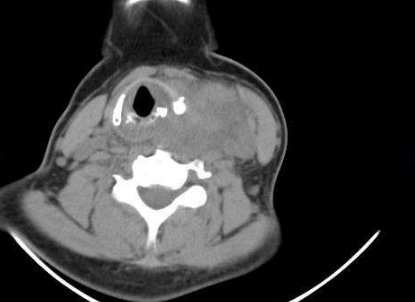

甲狀腺亢進圖片

甲亢脖子症狀